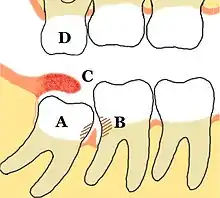

Impacted wisdom teeth are classified by the direction and depth of impaction, the amount of available space for tooth eruption and the amount of soft tissue or bone that covers them. The classification structure allows clinicians to estimate the probabilities of impaction, infections and complications associated with wisdom teeth removal.[26] Wisdom teeth are also classified by the presence of symptoms and disease.[27]